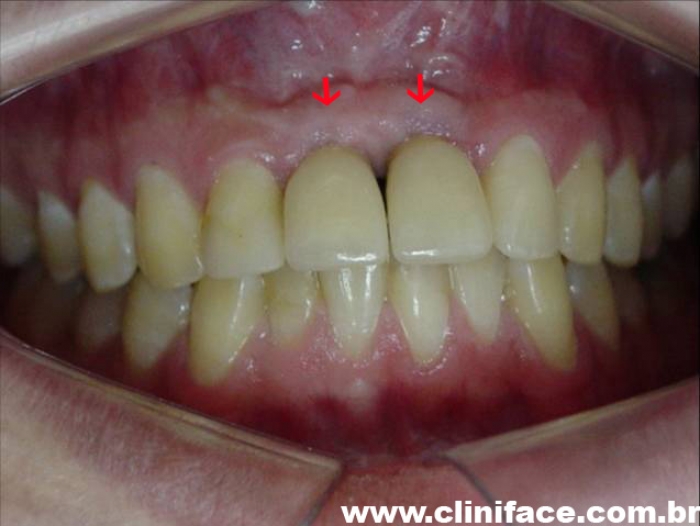

Dentes provisórios instalados